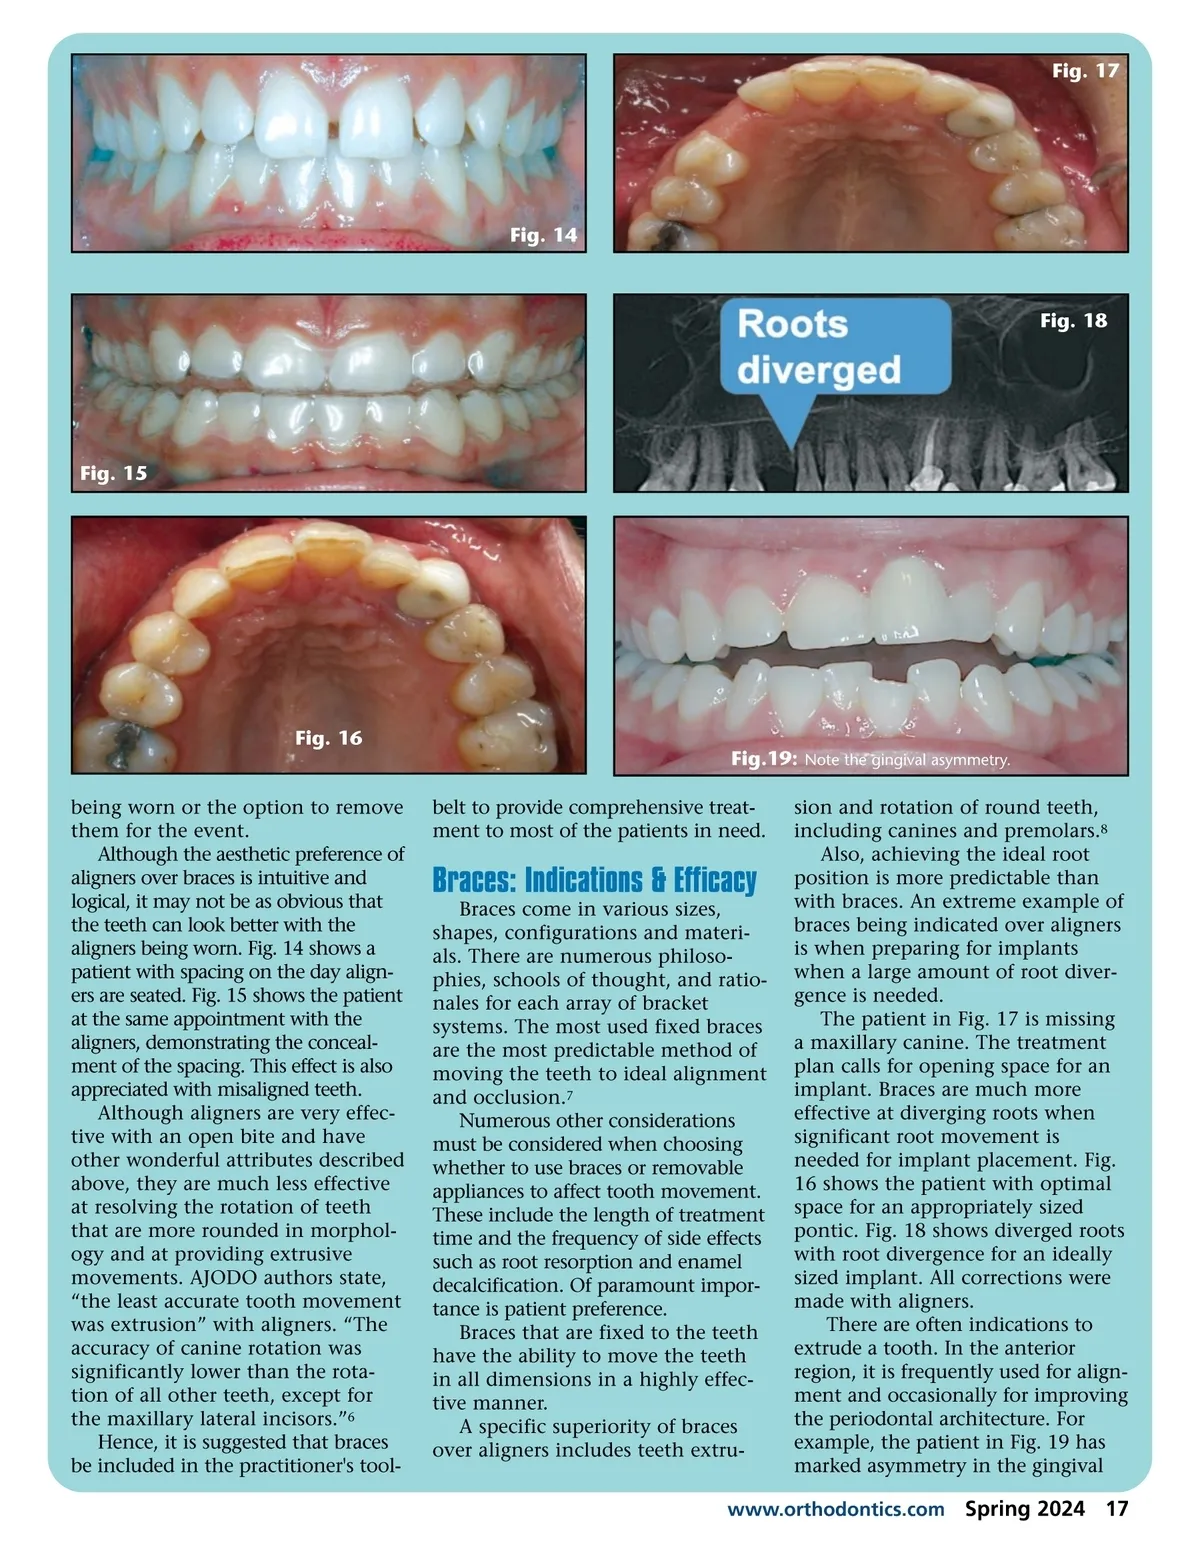

Fig. 11 Fig. 12 Fig. 13 from treatments as a child. Fig. 11 shows the extreme root resorption prior to initiating adult orthodon-tics. Since root resorption is much less frequent with aligners, the patient underwent comprehensive Orthodontics with aligners, success-fully resolving his malocclusion without additional resorption or clinical mobility. See post treatment in Figs. 12 and 13. The extreme example highlights the opportunity to treat patients previously deemed too high-risk. The patient was treated in the early days of aligners; hence, the align-ment could have been better, and the treatment time was two years, which was lengthy for an aligner patient with moderate crowding. A 2017 journal article validated the claim of minimal root resorp-tion in aligner patients. The root resorption was minimal and not clinically significant, as measured by pre-and post-treatment CBCT images. As the authors stated in the American Journal of Orthodon-tics and Dentofacial Orthopedics (AJODO), “We found…an extremely low incidence of root resorption and that the posttreat-ment position of the root apices relative to the palatal cortical plate was the strongest predictor of root resorption.” 4 Aligners are also indicated in patients with metal allergies or are opposed to having any metals placed in their mouths. The prefer-ence may be due to allergy, sensitiv-ity, or anticipated use of magnetic residence imaging. Orthodontic practitioners are aware of the occasional request for a quick improvement of malocclu-sion in preparation for a milestone event, such as a wedding. Often, minimally sought is an improve-ment of the misalignment without the fear of braces showing in photos. Published treatment times for aligner patients demonstrate shorter treatment durations. The average aligner treatment was reported to be six months shorter than braces. 5 Aligners are a good solution on two counts. Improved esthetics for the milestone event if aligners are 16 Spring 2024 JAOS

Journal of the American Orthodontic Society Spring 2024: Page 16